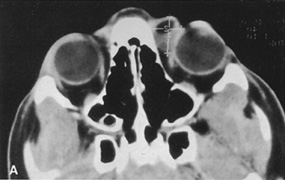

HISTORY AND PHYSICAL EXAMINATION A wide range of signs and symptoms may alert the ophthalmologist to involvement of the orbit by a pathologic process. These include proptosis or globe displacement; compressive optic neuropathy with visual field or visual acuity loss; refractive changes such as progressive hyperopia, restricted eye movements, and diplopia; optic disc changes, including pallor or edema; and fundus changes such as choroidal folds. These manifestations may be the consequences of a primary intraorbital disease or may occur secondary to involvement of the orbit by a process extending from the overlying soft tissues, periorbital sinuses, or intracranial cavity. All patients with suspected orbital pathology should have a thorough ophthalmic history and physical examination. Detailed questioning about the nature, onset, and progression of the chief complaint is necessary to formulate a differential diagnosis. Previous ocular and general medical history related to diseases, operations, medications, and family history should be obtained. A general review of systems will identify risk factors for related systemic diseases, such as hyperthyroidism, metastatic cancer, or lymphoma. A complete examination of the eye and periocular tissues is essential. Abnormal protrusion or displacement of the globe, extraocular motility disturbances, soft-tissue changes, and decreased corneal or periorbital cutaneous sensation should be specifically sought. Special attention always should be directed to evaluation of optic nerve function. Visual acuity testing alone is not sufficient because visual acuity often is preserved initially in patients with compressive optic neuropathy. All patients should be examined closely for detection of an afferent pupillary defect, abnormal color vision, or loss of contrast sensitivity. Formal perimetry should be performed to rule out peripheral field loss. If the presentation has been gradual, evaluation of old photographs may help establish the time course of the pathologic process. In selected cases, appropriate blood work to help identify orbital inflammatory or neoplastic processes also should be obtained. ORBITAL IMAGING Valuable information about the nature and extent of an orbital pathologic process is provided by imaging studies such as computed tomography (CT) scan, magnetic resonance imaging (MRI), and orbital echography. Better spatial resolution, ready accessibility, and lower cost make CT the preferred choice for orbital imaging in most cases. Orbital fat provides a natural contrast between most adjacent orbital structures on CT scanning, and orbital bones are visualized well. Computed tomography is essential for evaluation of the orbital bones because they cannot be imaged with MRI. Direct coronal or sagittal images are important to identify the relationship of a lesion to the optic nerve so that the surgical approach can be planned to avoid traversing the optic nerve (Fig. 1). Newer multislice helical CT scanners allow continuous acquisition of data so that a single rapid pass allows formatting in axial, coronal, and sagittal planes. Multislice CT provides shorter examination times with reduced motion artifact and radiation exposure when compared with conventional CT. Magnetic resonance imaging is useful in selected cases, especially when evaluating the orbital cranial junction. Significant bony artifact and a lack of orbital fat in the orbital apex make CT scan resolution of the orbital apex structures poor. Because cortical bone has low signal on MRI, there is no bone artifact when viewing the orbital apex on MRI. The lack of intervening fat in the apex to provide contrast is overcome on MRI because contrast is provided by the individual nuclear characteristics of each tissue so that the orbital apex structures are visualized well. Consequently, conditions that affect the optic nerve and chiasm, such as optic nerve meningioma and glioma, generally are evaluated with MRI rather than CT scan (Fig. 2). Use of a contrast agent such as gadolinium can further enhance the T1 signal intensity of lesions and is particularly helpful in imaging areas where there has been a breakdown in the blood–brain barrier. Because orbital fat produces a bright signal on T1-weighted images, orbital MR usually is performed with “fat suppression” to prevent masking of lesions. However, incomplete fat suppression can produce artifacts that may be misinterpreted as abnormal enhancement. A few other orbital conditions are better visualized with MRI than CT scanning.1–3 Often, organic foreign bodies, such as wood, are not imaged well with CT scan. These foreign bodies often are visible with MRI. However, care must be taken when imaging any metallic intraocular or intraorbital foreign body because the strong magnetic field of the MR scanner may cause the foreign body to shift position and damage surrounding structures. In some tumors and vascular anomalies, high blood flow is appreciated on MRI. This is caused by a lack of signal, known as a flow void, created by blood flowing rapidly through larger vessels. Tumors that originate in the brain and extend into the orbit secondarily, such as sphenoid wing meningioma, also are visualized well with MRI. However, bony detail and calcification within the meningioma are not imaged well. In unusual circumstances such as this, CT scan and MRI may prove to be complementary, and both techniques may be required to fully evaluate the orbital disease process. Orbital echography can provide useful information in the evaluation of orbital disorders. Because each tissue has its own acoustic characteristics, echography can provide a high degree of tissue contrast. Spatial resolution also is quite good. In some situations, echography can provide information not available on CT scan or MRI. These instances include detection and measurement of blood flow4 and intraoperative localization of small foreign bodies.5 Orbital echography requires specialized equipment and a large amount of expertise to obtain the detailed information that is readily available with CT scan or MRI; consequently, its use has decreased. Recent advances in orbital imaging have been summarized by Lee and colleagues.6 |